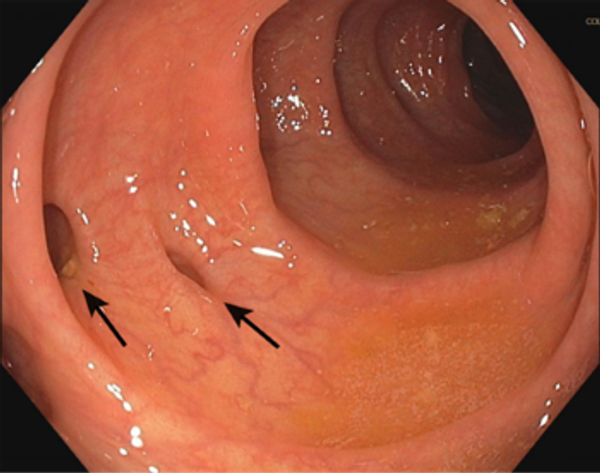

Leestijd: 6 minutenEen divertikel is een goedaardige uitstulping van de darmwand in de vorm van een zakje. Dit zakje is meestal het gevolg van een zwakke plek in de darmwand die, door een verhoogde druk in de darm, gaat uitstulpen. Waarschijnlijk is het niet genoeg eten van vezels, waardoor ontlasting minder soepel door de darm bewogen wordt, een belangrijke oorzaak van het ontstaan van één of meer divertikels.

Veel mensen hebben, vooral op een wat latere leeftijd, meerdere divertikels in de darm, maar merken hier weinig van, omdat ze geen klachten geven. Vaak worden ze dan ook per toeval ontdekt. Het hebben van meerdere divertikels wordt ook diverticulose genoemd.

Als iemand zich met (een aantal) bovenstaande klachten bij de huisarts meldt, doet deze meestal eerst een bloedonderzoek naar ontstekingswaarden. Vaak wordt er ook doorverwezen om een echografie van de onderbuik te laten maken. Tijdens dit onderzoek wordt de dikke darm, met behulp van radiogolven, in beeld gebracht en worden eventuele ontstekingen zichtbaar. Soms is het echter niet duidelijk dat het om diverticulitis gaat en zijn een CT-scan en/of een coloscopie (het met een flexibele slang waarin een camera zit, via de anus, in de darm kijken) noodzakelijk om een goede diagnose te kunnen stellen.